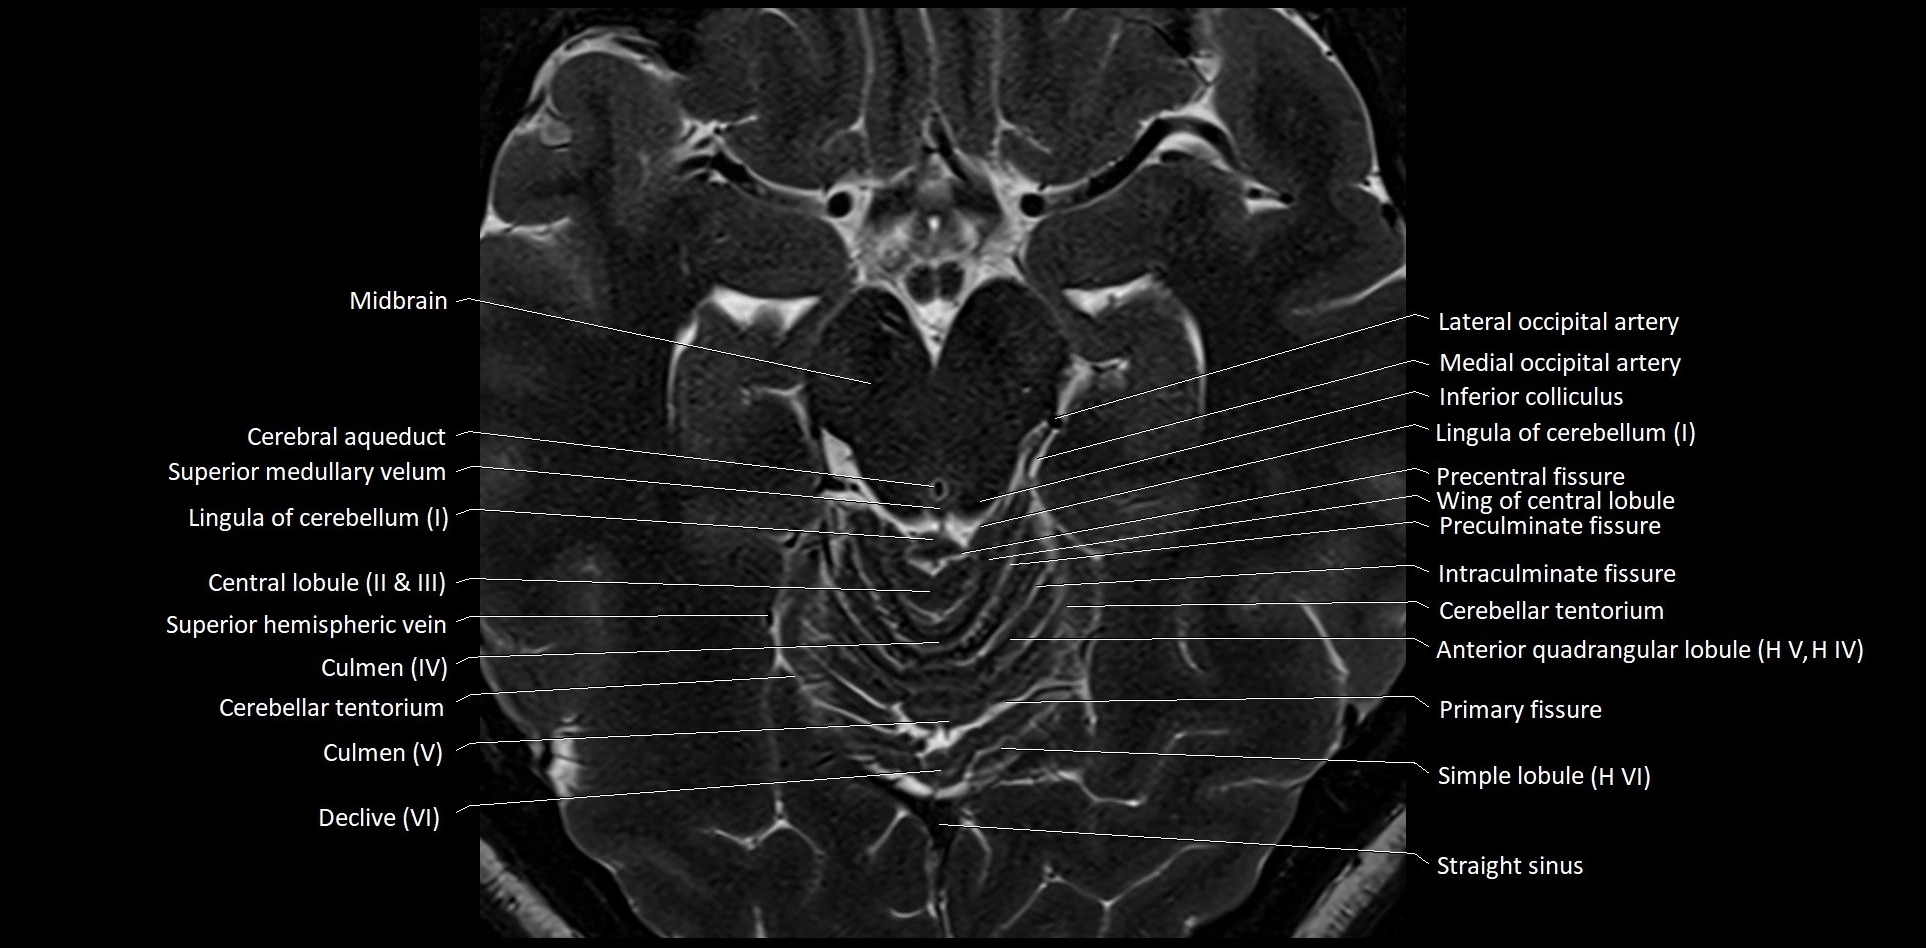

- Culmen

- Culmen (IV, V) of Cerebellum

- Declive

- Declive (VI) of Cerebellum

- Intraculminate fissure

- Lateral occipital artery

- Lingula of cerebellum

- Lingula of cerebellum (I)

- Medial occipital artery

- Precentral fissure

- Preculminate fissure

- Primary fissure

- Simple lobule

- Simple lobule (HVI) of cerebellum

- Straight sinus

- Superior cerebellar peduncle

- Superior medullary velum

- Wing of central lobule